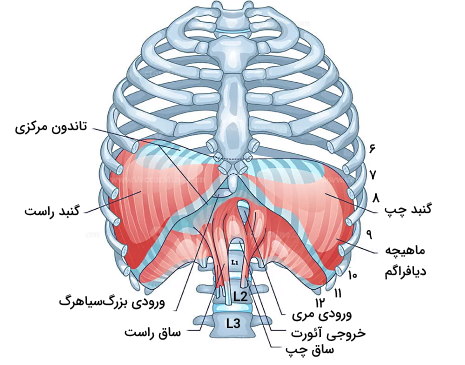

دیافراگم

ماهیچه اسکلتی دیافراگم پایین دندههای قفسه سینه قرار دارد. این ماهیچهای گنبدی قفسه سینه را از حفره شکمی و اندامهای گوارشی جدا میکند. به علاوه انقباض و انبساط حجم قفسه سینه را در دم و بازدمها تغییر میدهد. دیافراگم ماهیچهای صفحهای و بزرگ است که قسمتهای مختلف آن از مهرههای کمری، غضروفهای دندهای ۷-۱۰ و زائده زیفوئید شروع میشود. انقباض ماهیچه دیافراگم بهوسیله اعصاب حرکتی فرنیک تحریک میشود و سرخرگهای فرنیک پایینی بخش اصلی خون مورد نیاز آن را تامین میکنند.

دو برآمدگی (گنبد) این ماهیچه دو طرف پریکاردیوم قرار دارد و به دلیل وجود کبد گنبد سمت راست در حالت استراحت کمی بالاتر از گنبد چپ قرار میگیرد. ماهیچهای که از مهرههای کمری شروع میشود بخش تاندونی دیافراگم است که ساق راست و چپ این ماهیچه را تشکیل میدهد. ساق راست از مهرههای L1 تا L3 و دیسکهای بین مهرهای شروع میشود. بخشی از فیبرهای این ساق اسفنکتری در دهانه مری تشکیل میدهد. ساق چپ از مهرههای L1 و L2 و دیسکهای بین مهرهای شروع میشود. تاندونها با هم یکی شده و تاندون مرکزی را تشکیل میدهد. تاندون مرکزی به بافت فیبروزی پریکاردیوم متصل میشود.

شکاف سیاهرگی، مری و آئورت تنها راه ارتباطی بین قفسه سینه و حفره شکمی در دیافراگم است.

- شکاف سیاهرگی: بزرگسیاهرگ پایینی و شاخههای انتهایی اعصاب فرنیک از این شکاف وارد قفسه سینه میشود. این شکاف همسطح مهره T8 است.

- شکاف مری: مری، شاخههای راست و چپ عصب واگ، و شاخه چپ سرخرگ و سیاهرگ شکمی از این شکاف وارد حفره شکمی میشود. این شکاف همسطح مهره T10 است.

- شکاف آئورت: آئورت، سیاهرگ آزیگوس و مجرای لنفاوی قفسه سینه از این شکاف عبور میکند. این شکاف همسطح مهره T12 است.